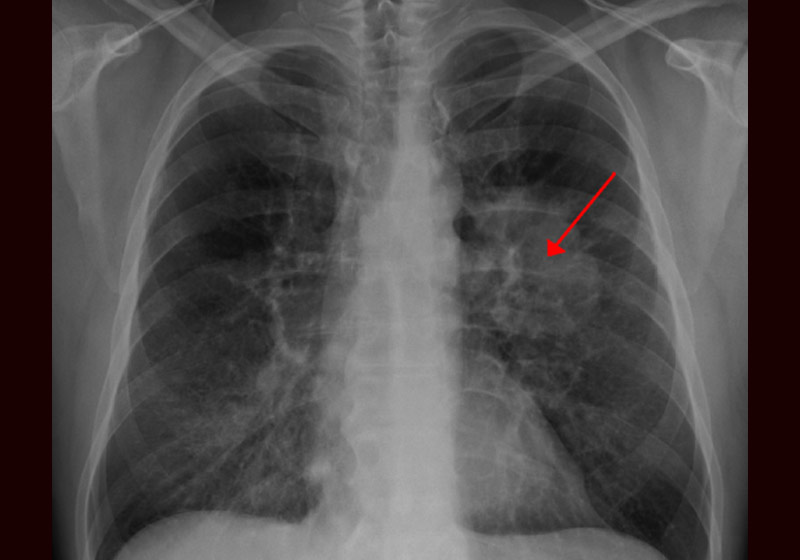

O paciente, que não teve o nome revelado, tem aproximadamente 40 anos. Ele foi hospitalizado após um tumor no pulmão esquerdo bloquear a artéria principal, levando ao colapso.

Durante a cirurgia, no mês passado, o homem continuou a respirar pelo pulmão bom, enquanto o outro era desconectado, limpo do tumor e reconectado – após inflá-lo para garantir que continuasse funcionando e que o tecido estava saudável.